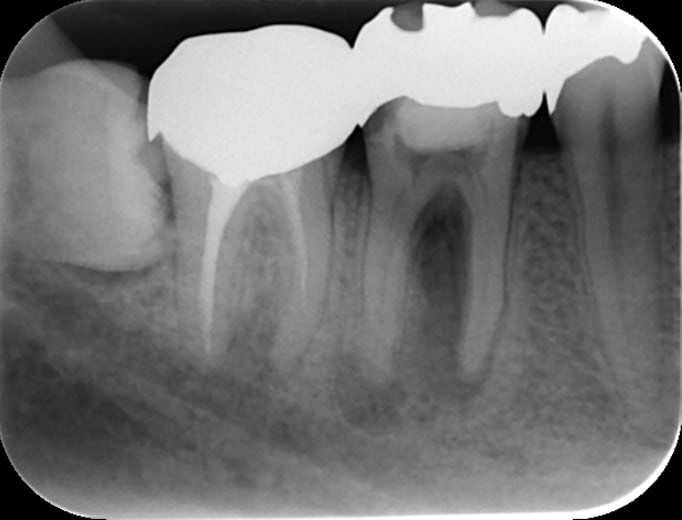

再根管治療(過去に神経の治療をした歯のやり直し)

すでに感染している。もしくは被せ直しをするために念のため歯の内部を再度きれいにする治療です。

術前(長い金属の棒を取る+感染を治すために紹介された)

術後(長い金属の棒はマイクロスコープ下で安全に除去し薬を詰めた状態。わずかに画像が変化し治癒してきている)

残念ながら初回の根管治療が上手くいかず再根管治療になると難易度が上がり、成功率は低下します。再根管治療は専門医に紹介すべき症例の1つです。